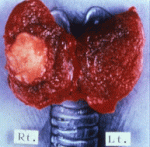

thyroid-cancer-papillaryThyroid cancer compensation for Fukushima plant worker http://www.asahi.com/ajw/articles/AJ201612170027.htmlBy YURI OIWA/ Staff Writer December 17, 2016 A man who developed thyroid gland cancer after working at the stricken Fukushima No. 1 nuclear plant has for the first time won the right to work-related compensation.

While the case ranks as the third time a worker at the Fukushima plant has been recognized as eligible for work-related compensation because of cancer caused by radiation exposure, it is the first instance involving thyroid gland cancer.

The man in his 40s, an employee of plant operator Tokyo Electric Power Co., worked at the Fukushima plant after the triple meltdown triggered by the 2011 Great East Japan Earthquake and tsunami. He was diagnosed with thyroid gland cancer in April 2014.